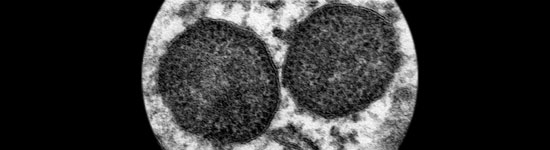

El PCV2 se ha ido asociando cada vez a más patologías, denominadas colectivamente enfermedades asociadas a PCV2 (PCVDs), como ES-PCV2, EP-PCV2, EE-PCV2, ER-PCV2, IS-PCV2 y SDNP.

Novedades sobre las vías de excreción, rutas de transmisión, factores de riesgo, etc y la explicación de porqué PCV2 se convierte en un virus patógeno.